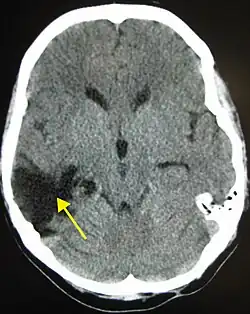

One of the top causes of death worldwide, strokes are disruptions of the blood supply to the brain. These disruptions can be triggered by a variety of ways, the most common of which are the rupturing of an artery (or hemorrhage), or blockages, which may either by from clots or other obstructions. Whatever the immediate cause, obstruction of the vascular system delivering blood to the brain can quickly lead to the death of cells in the affected areas. Like traumatic brain injury, the exact symptoms and consequences of a stroke depends on the region most affected, however there are some common characteristics. Paralysis or weakness on one side of the body- usually manifested in slurring of speech or drooping of the face- is very common since usually the blocked artery will be responsible for delivering blood to one specific brain hemisphere.

If medical attention is not administered quickly enough or if the stroke is severe enough, the damage to the brain may be permanent and can easily cause coma, paralysis, or death. Even if these more extreme consequences are avoided, in many cases the brain is unable to make a full recovery of the injured region and thus cognitive and functional deficits may remain. These can be seen in difficulties in coordinating fluid movement, psychological changes, or trouble with speech. Most of these areas however are at least somewhat amenable to therapy and may be recovered provided the damage was not too severe.